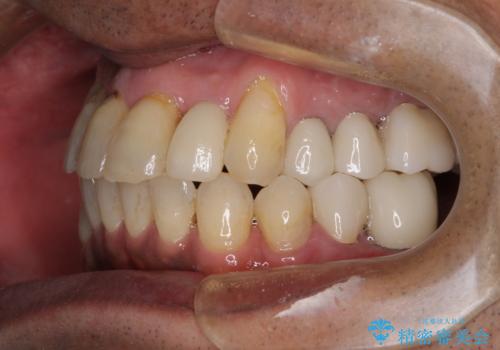

歯槽骨の再生治療を行ったため、外科処置後の静置期間がながくなり、4年弱の治療期間となりました。

初診来院時には矯正治療を行うことは想像していなかったようで、治療後には咬みやすさだけでなく、前歯が大変審美的に仕上がり、患者様には大変満足していただきました。